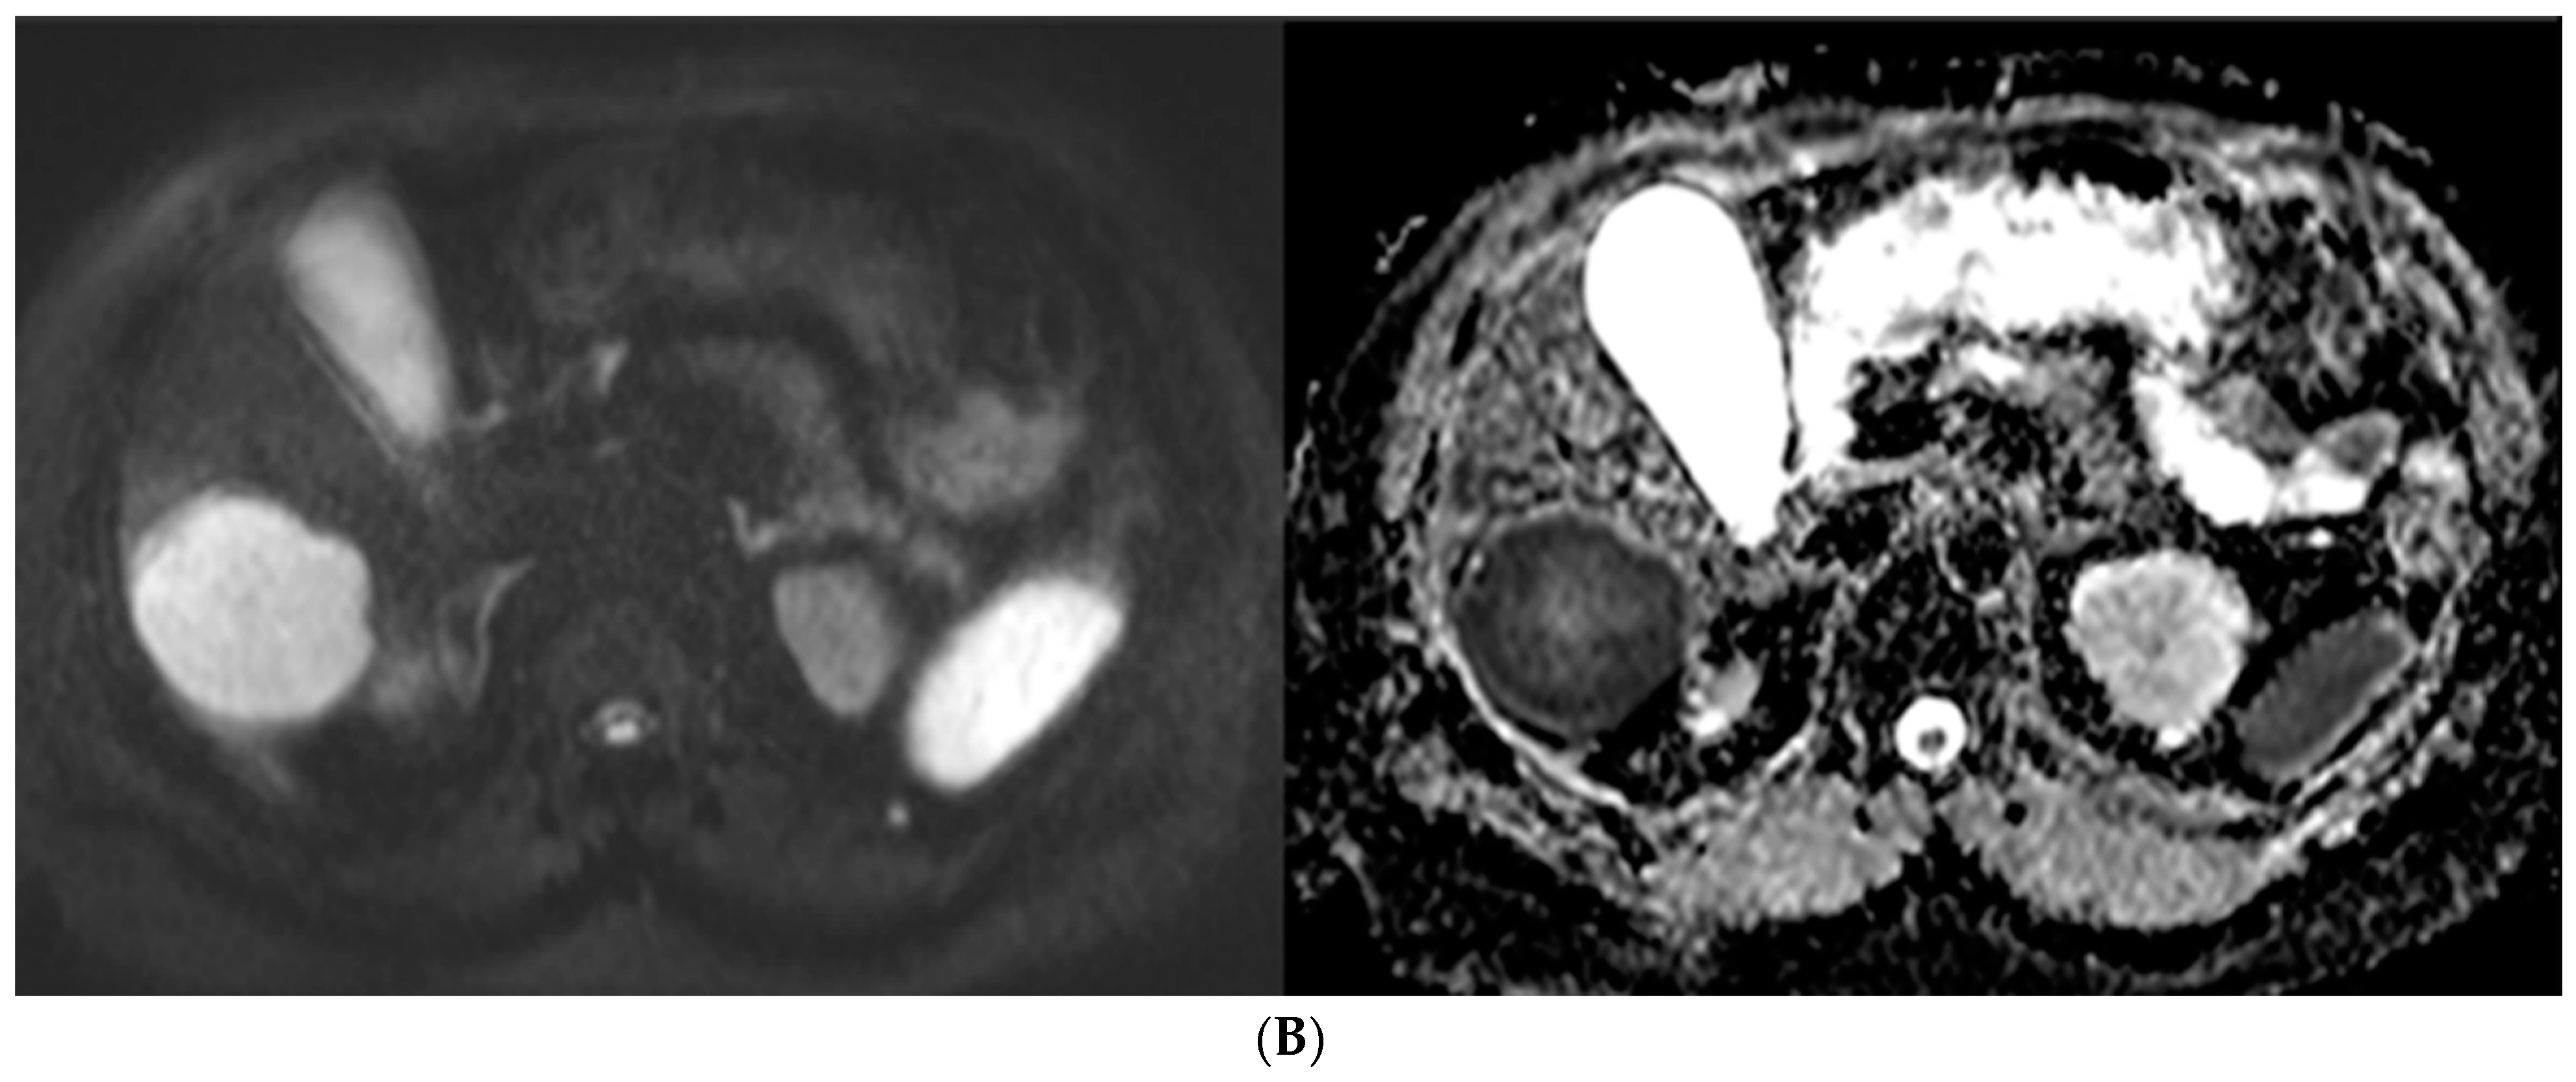

Figure 5.

57-year-old man with well-differentiated G2 pancreatic neuroendocrine tumor referred for initial staging. (ADC = Apparent diffusion coefficient). (A) Axial 68Ga-DOTATATE PET (left) and fused PET/CT (right) images show intensely 68Ga-DOTATATE avid segment 6 deposit (green circle within metastasis represents region of interest, SUVmax, 45.0). (B) High signal intensity is seen on diffusion-weighted MR image with b value = 600 s/mm2 (left), and corresponding image on ADC map shows marked hypointensity (right).

Overall, DT-PT and pMR showed substantial agreement (Cohen’s kappa score: 0.757 (0.538, 0.975)). When the four outliers were excluded, agreement between the studies was nearly perfect (Kappa score: 0.945 (0.910, 0.980)). A correlation was found between lesion size on pMR and detection on DT-PET (odds ratio = 3.28; 95%CI: 1.1, 9.84). No significant relationships between modified Krenning score on DT-PET and T2 signal intensity, DWI, arterial enhancement, or washout were seen. Metastases with restricted diffusion on pMR had higher maximal SUVmax on DT-PET (p = 0.003) (Figure 5).